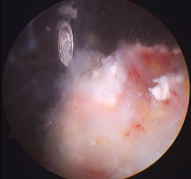

관절경수술 석회화건염 이미지

• 일상생활에 지장이 있을 정도로 심한 통증이 있는 경우에는 관절내시경 수술로 내부의 석회성 물질을 제거하고 염증 부위를 절개 합니다.